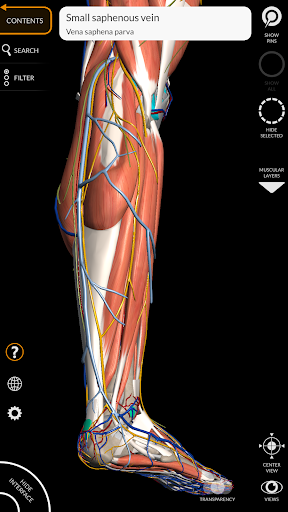

"Anatomy 3D Atlas" дозволяє легко та інтерактивно вивчати анатомію людини.

Завдяки простому та інтуїтивно зрозумілому інтерфейсу можна спостерігати кожну анатомічну структуру під будь-яким кутом.

Анатомічні 3D-моделі особливо деталізовані та мають текстури з роздільною здатністю до 4k.

Поділ за регіонами та попередньо визначені види полегшують спостереження та вивчення окремих частин або груп систем і зв’язків між різними органами.

• Обертайте та збільшуйте кожну модель Тривимірний простір

• Можливість приховування або ізоляції однієї чи кількох вибраних моделей

• Візуалізація м’язів через рівні шарів від поверхневих донизу до найглибших

• Вибравши модель або шпильку, з’явиться відповідний анатомічний термін